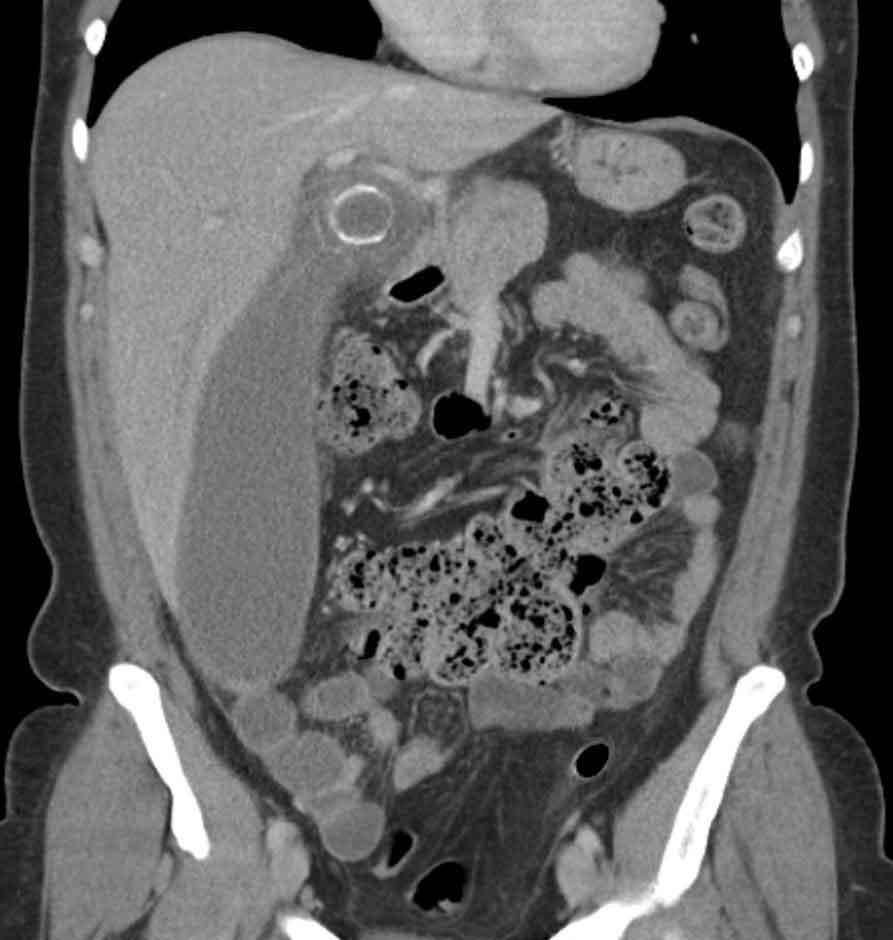

Imaging showing dilated common bile duct due to obstructing gallstone

Complications & Planning

CT Abdomen

Used when complications are suspected — perforation, abscess, pancreatitis, or when surgery needs detailed anatomy. Not the first-line test for simple gallstones, but invaluable for emergency and complex cases. Blood tests (LFT, amylase, CBC) are essential companions to all imaging.